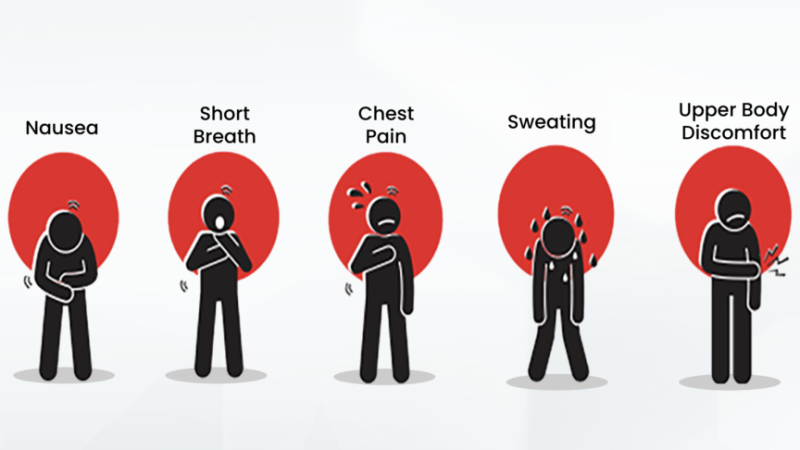

نشانههای حمله قلبی

نشانههای یک حملهی قلبی شامل موارد زیر هستند:

نشانههای حمله قلبی...